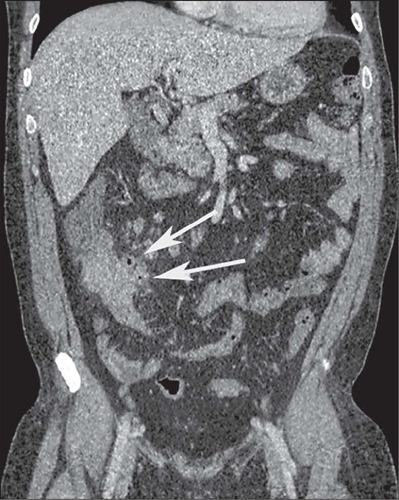

Crohn's disease is an inflammatory bowel disease that can affect any segment of the gastrointestinal tract. It has a variable clinical course, with alternating periods of disease activity and remission. Because the incidence and prevalence of Crohn's disease have been increasing, evaluation by imaging methods has become more important. The most widely used methods are computed tomography enterography, magnetic resonance enterography (as an elective examination), and contrast-enhanced computed tomography (in the context of emergency). Computed tomography enterography and magnetic resonance enterography are useful for diagnosis, follow-up, evaluation of complications, and prognosis. Both can be used in order to evaluate the small bowel loops and the associated mesenteric findings, as well as to evaluate other abdominal organs. They both also can detect signs of disease activity, fibrosis, penetrating disease, and complications. The interpretation of such changes is essential to the multidisciplinary approach, as is the standardization of the nomenclature employed in the reports. In this paper, we review and illustrate the imaging findings of Crohn's disease, using the standardized nomenclature proposed in the multidisciplinary consensus statement issued by the Society of Abdominal Radiology, the Society of Pediatric Radiology, and the American Gastroenterology Association, with recommendations for descriptions, interpretations, and impressions related to those findings.

克罗恩病是一种炎症性肠病,可累及胃肠道的任何节段。其临床病程多变,疾病活动期和缓解期交替出现。由于克罗恩病的发病率和患病率一直在上升,通过影像学方法进行评估变得更加重要。最常用的方法是计算机断层扫描小肠造影、磁共振小肠造影(作为选择性检查)和增强计算机断层扫描(在急诊情况下)。计算机断层扫描小肠造影和磁共振小肠造影对诊断、随访、并发症评估及预后判断均有帮助。两者均可用于评估小肠肠袢及相关肠系膜表现,以及评估其他腹部器官。它们还都能检测疾病活动、纤维化、穿透性病变及并发症的征象。对这些改变的解读对于多学科诊疗方法至关重要,报告中使用的命名标准化也同样重要。在本文中,我们使用腹部放射学会、儿科放射学会和美国胃肠病学会发布的多学科共识声明中提出的标准化命名,回顾并阐述克罗恩病的影像学表现,并对与这些表现相关的描述、解读及印象给出建议。